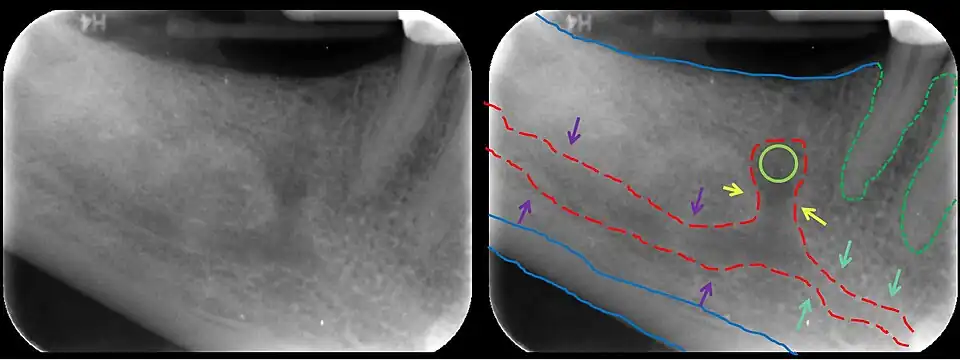

![]() The mandibular incisive canal (indicated here by coral green arrows) continuing anteriorly (to the right) from the mandibular canal (purple arrows) after the mental foramen (light green circle). | |

The mandibular incisive canal is a bilaterally paired bony canal within the anterior portion of the mandible that extends from the mental foramen (usually) to near the ipsilateral lateral incisor teeth.[2]

The inferior alveolar nerve splits into its two terminal branches within the mandibular canal: the mental nerve (which exits the mandible through the mental foramen), and the incisive nerve which represents an anterior continuation of the inferior alveolar nerve and continues to course within the mandible in the mandibular incisive canal. The incisive nerve provides innervation to the mandibular first premolar, canine and lateral and central incisors.[2] The incisive nerve either terminates as nerve endings within the anterior teeth or adjacent bone, or may join nerve endings that enter through the tiny lingual foramen.

The incisive canal is typically found within the middle third of the mandible in an apico-coronal dimension, reaching the midline 18% of the time.[3]